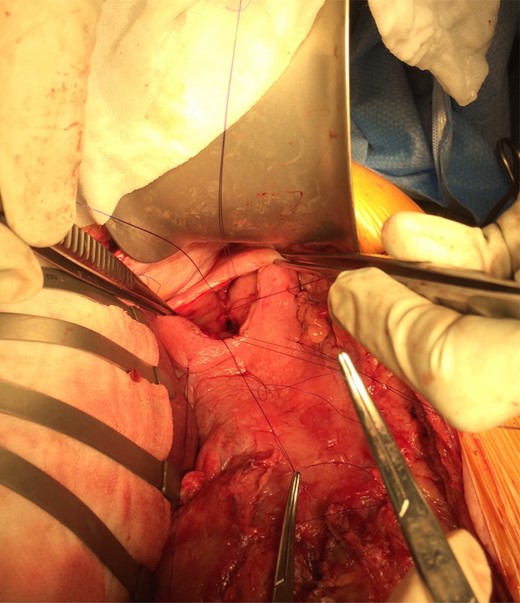

A 60-year-old female was admitted for management of hematemesis. Three weeks prior, she sustained a flail chest, right hemothorax, splenic laceration, mesenteric injury, and lumbar and thoracic vertebral fractures in a motor-vehicle accident. She initially underwent a trauma laparotomy and right hemicolectomy. Significant hematemesis occurred 4 days after admission to the rehabilitation ward, and the patient was transferred to the intensive care unit (ICU), where a gastroscopy was performed. A large clot was observed in the fundus; however, there was no active bleeding. A Sengstaken–Blakemore (SB) tube was inserted and the gastric balloon inflated under endoscopic vision, and 6 units of packed red blood cells, 4 units of fresh frozen plasma, 2 units of platelets and 10 units of cryoprecipitate were transfused. Hemodynamic stabilization was achieved, and serum hemoglobin rose from 61 to 89 g/dl . A repeat gastroscopy the following day demonstrated the fundal clot plus a large MWT at gastroesophageal junction (GEJ) (Fig. 1). Adrenaline (1:10 000) was injected around the tear, and the SB tube was removed. The patient subsequently developed a pulmonary embolism, which was treated with an inferior vena caval filter. On Day 5 after transfer to the ICU, the patient was discharged to the regular ward. She was receiving proton pump inhibitor (PPI) therapy. Hematemesis recurred on Day 8, and the patient was intubated because of hemodynamic instability. Gastroscopy was performed after massive transfusion resuscitation, and the large fundal clot and MWT were again noted. Hemostatic powder (EndoClot®) was applied over the probable location of the fundal ulcer as well as MWT though there was no active bleeding.

A large Mallory–Weiss tear and large fundal clot were observed during gastroscopy.